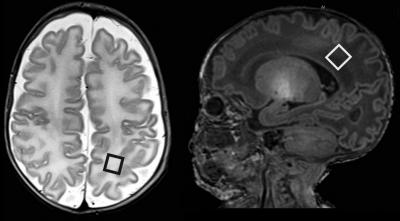

Patients in the study included 43 infants (24 male) born at less than 32 weeks gestation and admitted to the neonatal intensive care unit (NICU) at the University College of London between 2007 and 2010. Dr. Kendall and his research team performed magnetic resonance imaging (MRI) and MR spectroscopy (MRS) exams on the infants at their approximate expected due dates (or term-equivalent age). MRS measures chemical levels in the brain.

The imaging studies were focused on the white matter of the brain, which is composed of nerve fibers that connect the functional centers of the brain.

Statistical analysis of the MRS results and Bayley Scales scores revealed that the presence of two chemical ratios—increased choline/creatine (Cho/Cr) and decreased N-acetylaspartate/choline (NAA/Cho)—at birth were significantly correlated with developmental delays one year later.

"Low N-acetylaspartate/choline and rising choline/creatine observed during MRS at the baby's expected due date predicted with 70 percent certainty which babies were at high risk for motor development problems at one year," Dr. Kendall said.